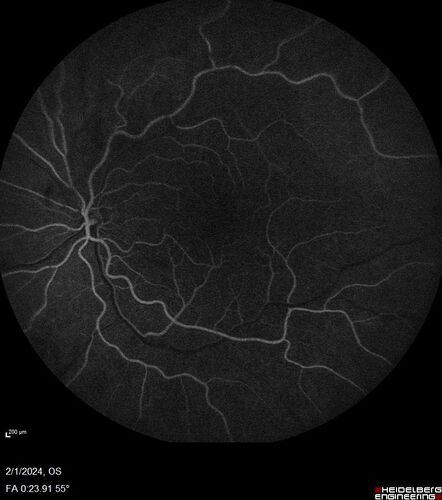

71 year old female with 3 months of vision loss and not feeling well.  She has been bruising on her legs.  Her vision was 20/100 in each eye with macular edema.  She was treated with Avastin and her CBC was checked.  She had a WBC of 267 thousand and was diagnosed with CML.

Chronic Myelogenous Leukemia and Diabetic Macular Edema